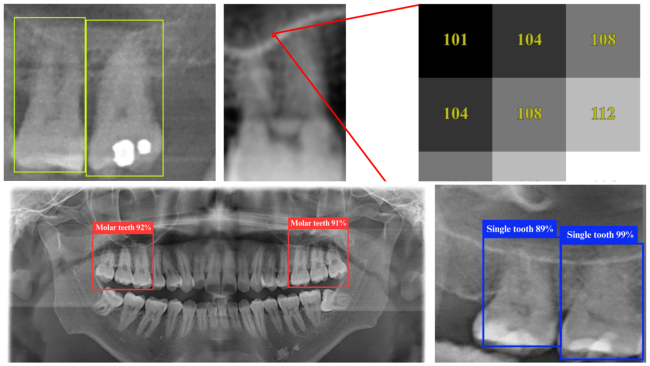

DPR dental X-ray images sampled using the YOLO algorithm

AI dental assistant reads X-rays with near-perfect accuracy